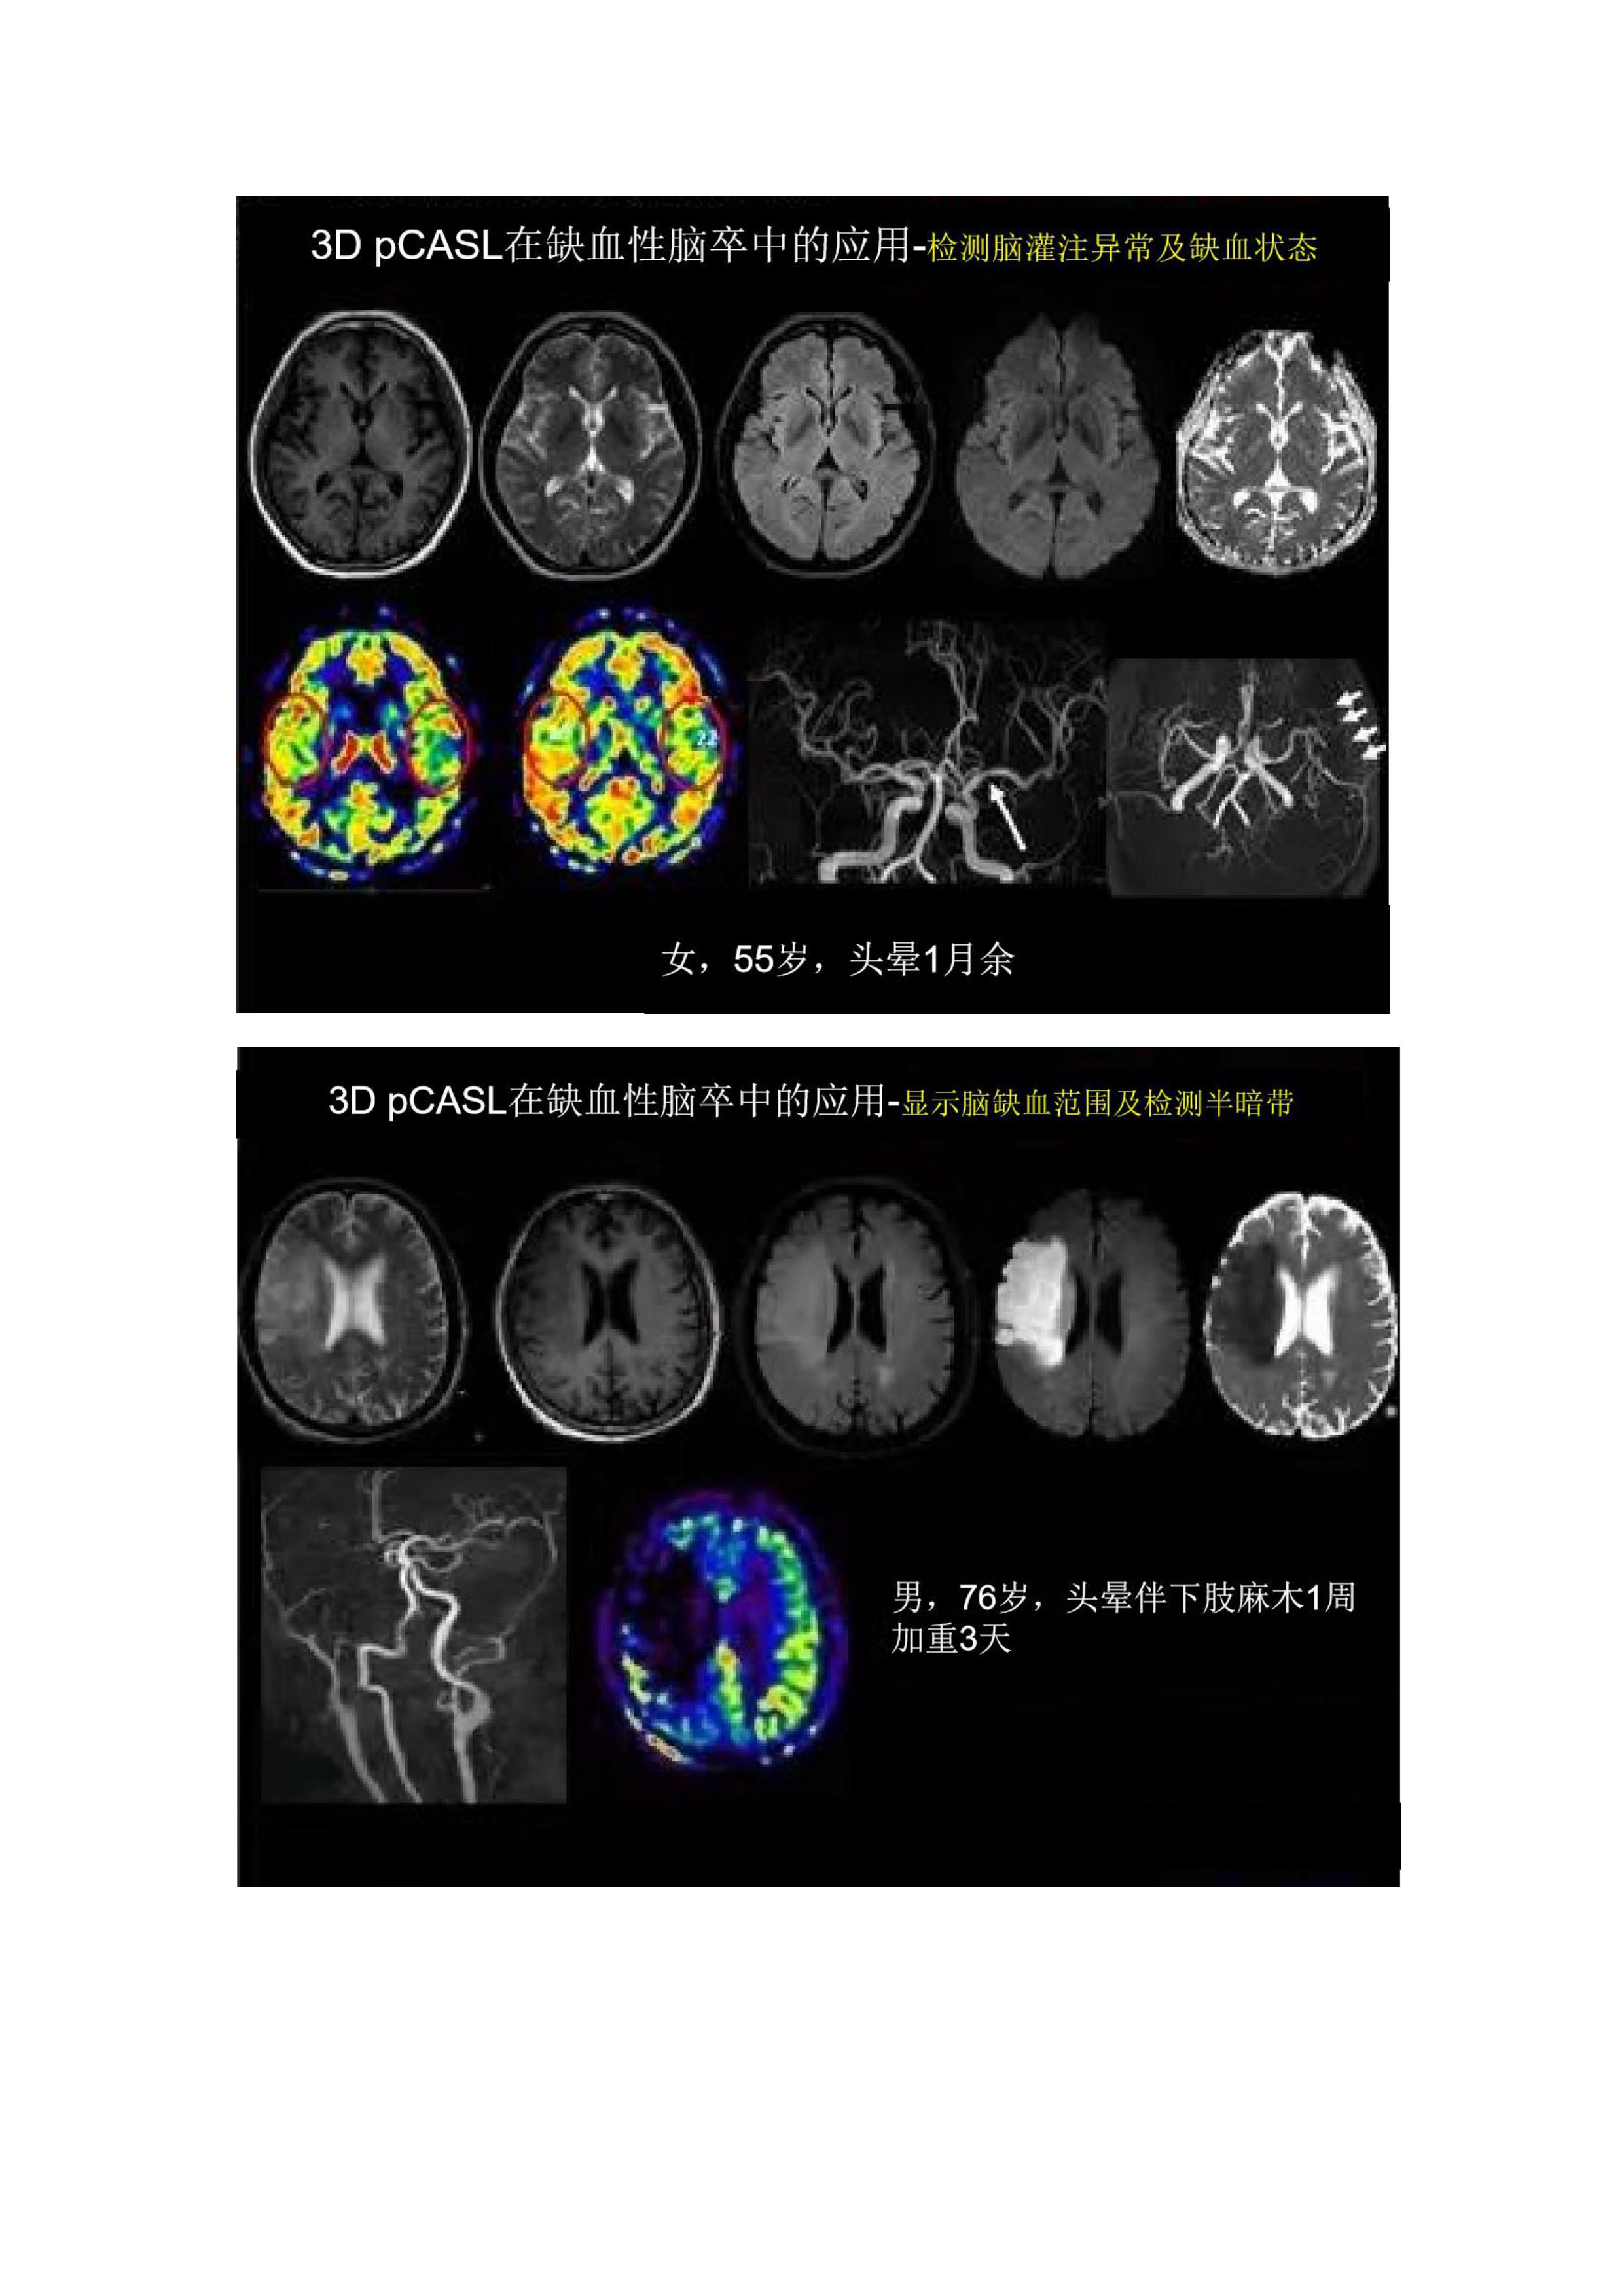

影像科 新技術(shù)臨床應(yīng)用周刊第6季